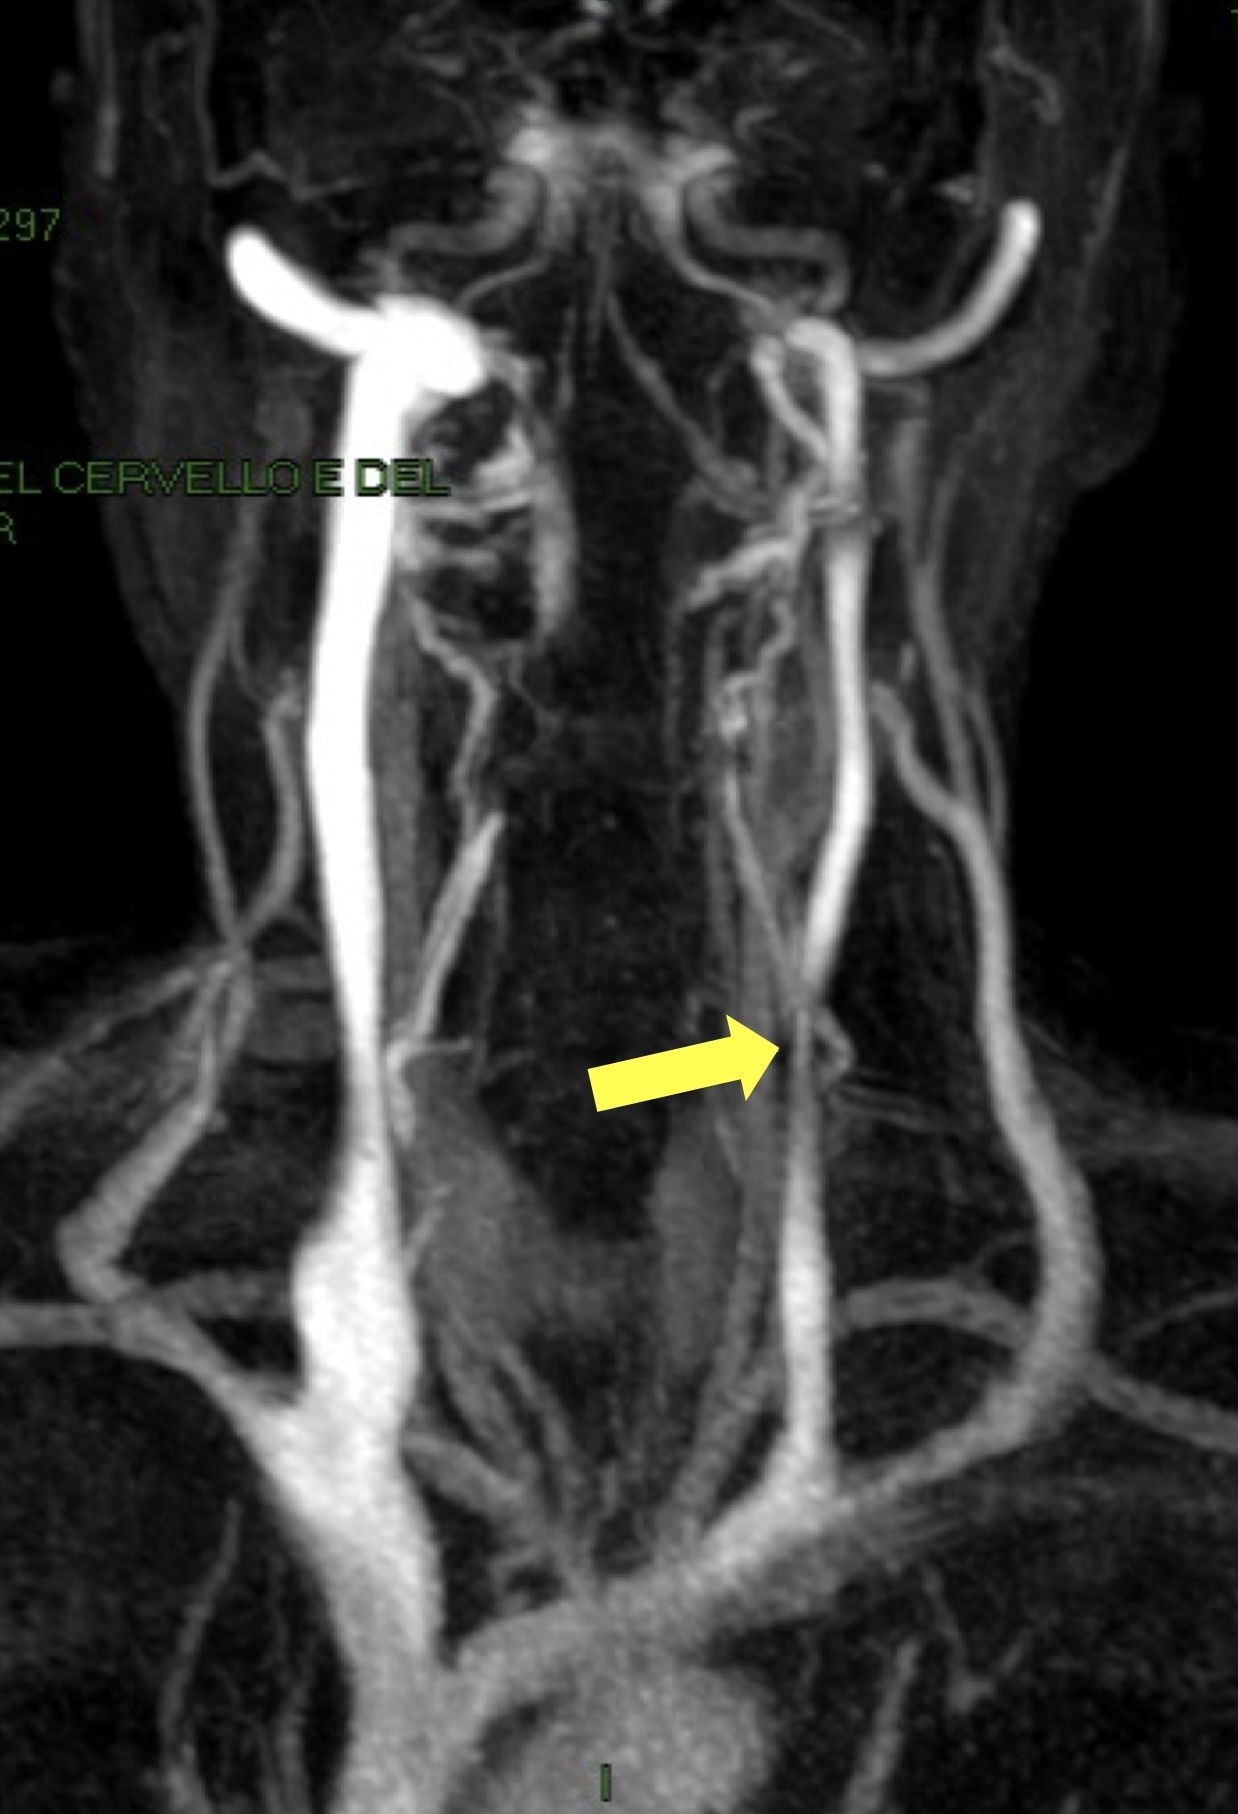

FOTO: Risonanza Magnetica delle vene cerebrali. La freccia gialla dimostra un restringimento della vena giugulare interna, caratteristico della CCSVI